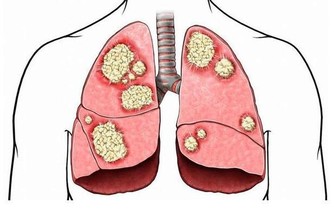

第二型糖尿病可能是胰臟累積過多脂肪所造成的,

適度減少脂肪量,病症也會跟著改善。

胰臟位於胃的後方,

負責分泌胰島素以維持血糖穩定。

第二型糖尿病患者的胰島素分泌不足,

而且無法正常發揮功能。